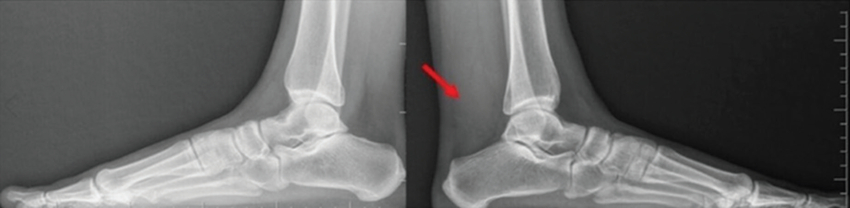

Se realizaron radiografías de perfil comparativas de ambos tobillos (Fig. 1). En el tobillo izquierdo se evidenció una opacidad en región posterior, que se extiende al sector distal de la pierna, con ocupación del triángulo de Kager.

En la radiografía perfil de tobillo, se presenta como radioopacidad de partes blandas, que ocupa el espacio de Kager, sin anomalías óseas asociadas.